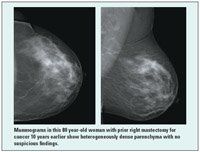

In the ongoing trial, women with dense breast tissue in at least one quadrant were scanned at 21 sites; 2,637 have completed at least 12 months of follow-up. More than half (53%) had a personal history of breast cancer, reported Wendie Berg, MD, PhD, and colleagues (JAMA 299:2151-2163, 2008). Dr. Berg is from American Radiology Ser vices, Johns Hopkins Green Spring, Lutherville, Maryland. ACRIN 6666 was funded by the Avon Foundation and the National Cancer Institute.